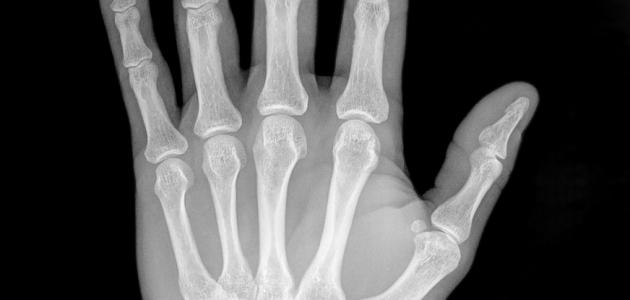

واستطاع رونتغن اكتشاف أشعّة إكس في عام 1895م، حين كان يجري تجربة تدفُّق التيّار الكهربائيّ في أنبوب زجاجيّ مُفرغ جزئيّاً من الهواء، وهو أنبوب أشعّة الكاثود؛ حيث لاحظ أنّ هناك ضوءاً قد نتجَ عن قطعة قريبة من البلاتين، وذلك عند تشغيل الأنبوب، فخرجَ بنظريّة، وهي أنّه عند اصطدام الإلكترونات (أشعّة الكاثود) بجدار الأنبوب الزجاجيّ، تظهرُ أشعّة مجهولة تُسبِّب وميضاً عند اصطدامها بالمادّة، ومن خلال عدّة ملاحظات، اكتشف أنّ هذا النوع من الأشعّة شفّاف لبعض الموادّ، مثل: الخشب، والورق، والألومنيوم، كما أنّ له تأثيراً في لوحات التصوير الفوتوغرافيّ، وهو لا يحمل أيّة خاصّية من خصائص الضوء، مثل: الانعكاس، أو الانكسار، ونتيجة لهذا، اعتقد بشكل خاطئ أنّه لا علاقة لهذا النوع من الأشعّة بالضوء، ونظراً لطبيعة هذه الأشعّة المجهولة، فقد أطلق عليها اسم أشعّة إكس، حيث التقطَ أوّل صورة باستخدام هذه الأشعّة لعظام يد زوجته.[٣]

بسبب مقدرة أشعّة إكس على اختراق موادّ مُعيَّنة، يتمّ استخدامها في عمليّات التفتيش الأمنيّ، وعند نَقْل البضائع والركّاب؛ حيث تسمحُ هذه الأشعّة، ومن خلال أجهزة الكَشْف عن الصور الإلكترونيّة، بتصوير محتويات الحقائب، والأمتعة، كما أنّها تُستخدَم في تصوير العِظام، وهي تُستخدَم كطريقة غير مُؤلِمة؛ لتشخيص المرض، ومراقبة العلاج، إضافة إلى أنّها تساعد في دَعْم العاملين في المجال الطبّي عند إدخالهم دعامات، أو أيّة أجهزة داخل الجسم، كما أنّ لها دوراً في علاج الأورام، وإزالة الانسدادات، والجلطات الدمويّة؛ وذلك لأنّ أشعّة إكس المُؤينة تُرسِّب كمّيات كبيرة من الطاقة في منطقة صغيرة؛ إذ تُجرِّد هذه الطاقة الإلكترونات من الذرّات، وهذا يؤدّي إلى تغيُّر في خصائصها الكيميائيّة، وكَسْرٍ للروابط الجزيئيّة، وبالتالي تَلَف الخلايا، أمّا إذا تمّ توجيهها إلى الخلايا السرطانيّة، فإنّها سوف تقتلها.[١]

ويلجأ الطبيب إلى استخدام الأشعّة السينيّة؛ للمراقبة، ولتشخيص مرض مُعيَّن، أو مراقبة تطوُّر مرض تمّ تشخيصه، أو للتحقُّق من مدى فعاليّة ونجاح علاج ما، ولالتقاط صورة باستخدام أشعّة إكس، يتمّ ارتداء ملابس فضفاضة؛ لتحريكها بسهولة، بالإضافة إلى أنّه لا بُدّ من نَزْع أيّة مجوهرات، أو أيّ عناصر معدنيّة، وقد تستدعي الحاجة تناوُل مادّة مُتبايِنة، وظيفتها المساعدة في تحسين نوعيّة الصورة، حيث قد تحتوي هذه المادّة على مُركَّبات اليود، أو الباريوم.[٢]